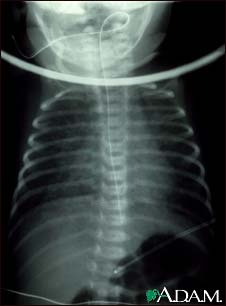

Totally anomalous pulmonary venous return, X-ray

Totally anomalous pulmonary venous return (TAPVR) is a form of congenital heart disease. This x-ray shows an enlarged heart, a large liver, and increased size of the lung blood vessels (pulmonary vascularity).